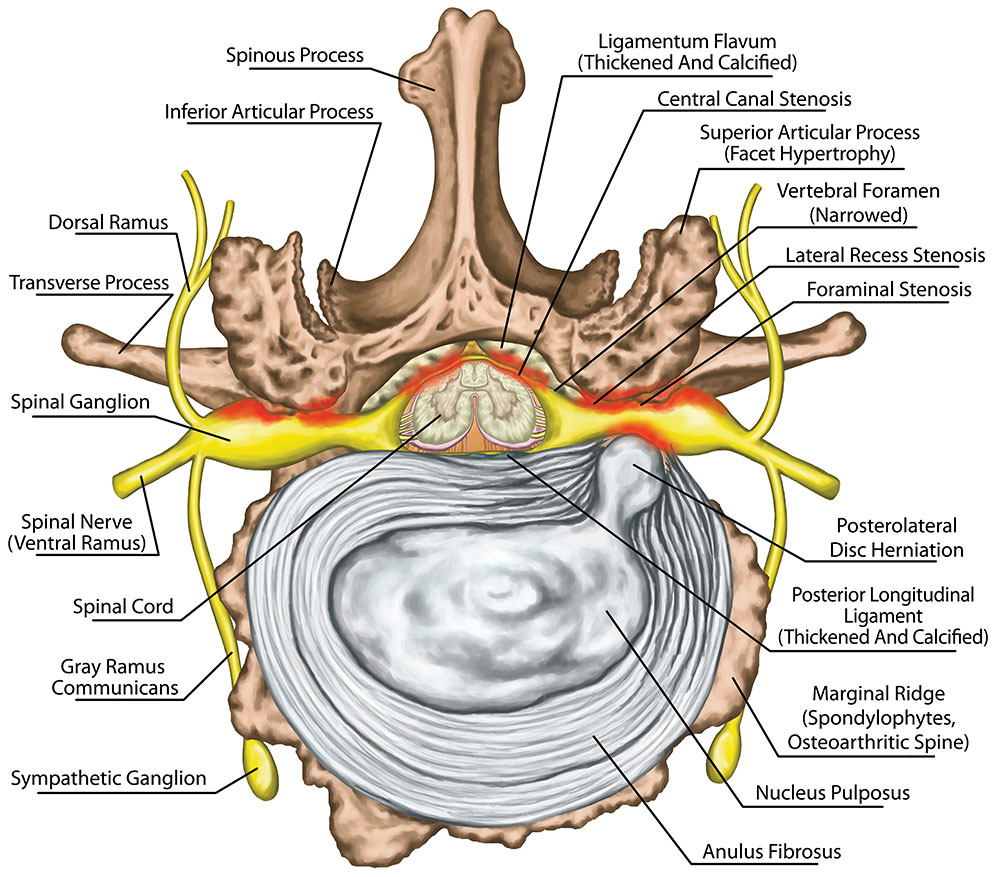

HWS Syndrom – Ursachen | Symptome | Behandlungen

Abbildung 2: HWS

Pin auf anatomie

Abbildung 6: HWS – CT

HWS-Syndrom: Symptome und Behandlung

HWS-Syndrom behandeln: Ursachen, Behandlung und Übungen | Hws syndrom …

Chirotherapie – Manuelle Medizin in der HNO Praxis Dr. Axel Suhrborg …

A Trip Back in Time: How People Talked About Herniated Disc In Neck 20 …